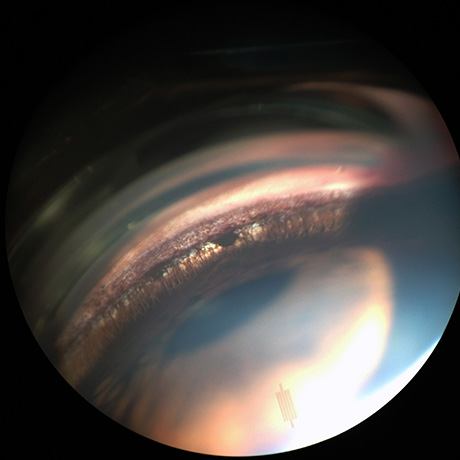

Na Oftalvet dispomos de equipamento avançado, de última geração, que permitem o diagnóstico das mais variadas doenças que afectam o globo ocular e seus anexos.